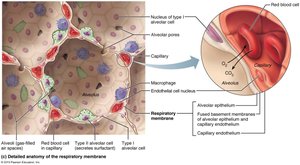

Respiratory Zone: Alveoli and Gas Exchange

Alveoli are the primary sites of gas exchange, lined by simple squamous epithelium. Their close association with capillaries allows for efficient diffusion of oxygen and carbon dioxide.

Type I Alveolar Cells: Squamous epithelial cells for gas exchange.

Type II Alveolar Cells: Produce surfactant to reduce surface tension and prevent alveolar collapse; secrete antimicrobial proteins.

Alveolar Macrophages: Engulf debris and pathogens.